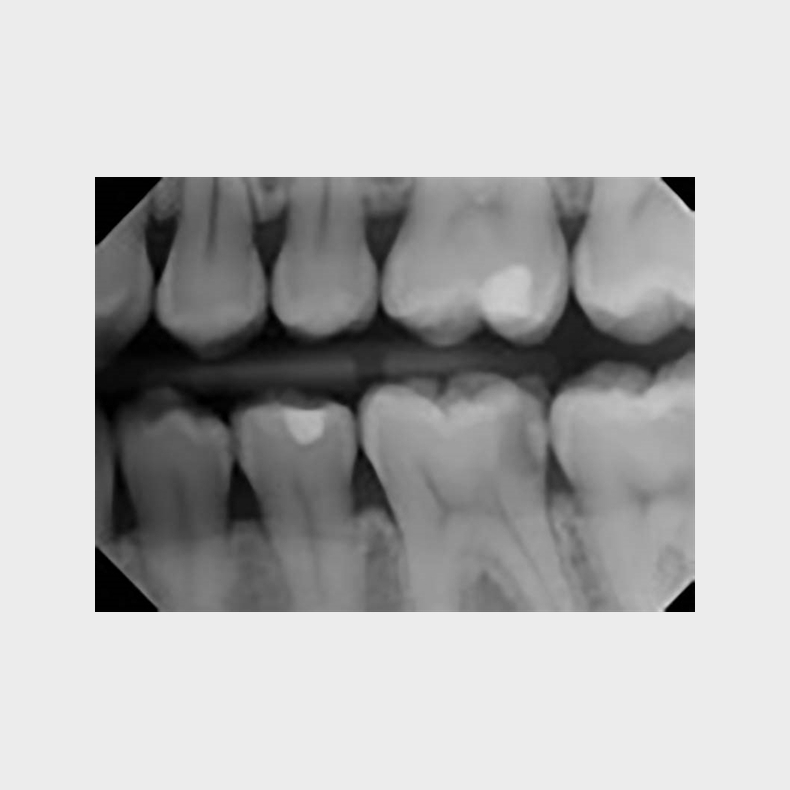

Der stilles nu krav om, at tubus på intraorale røntgenapparater skal have samme facon som en billedreceptor (rektangulært) og med et reduceret strålefelt på max. 4 x 5 cm.

Vi medbringer et røntgenfantom til øvelserne, så I kan lave røntgenoptagelser og evaluere dem sammen.

• Optage intraorale røntgenbilleder med brug af parallel- og vinkelhalveringsteknik.

• Kvalitetssikre og evaluere egne optagelser